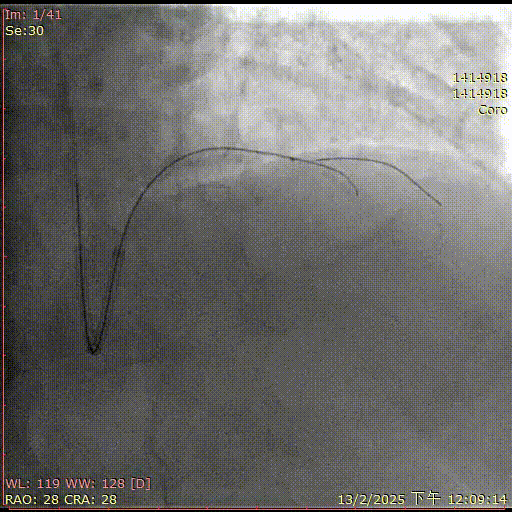

官学强教授团队

基本情况:患者,男,68岁,因“活动后胸闷气促5月”入院。

简要病史:2021年12月造影:前降至近段次全闭塞,导丝送至前降至远段,IVUS见“T-F-T”,中段位于内膜下,予球囊扩张。2025年2月复查冠脉造影见前降至开口闭塞,右管来源侧枝供应远段。J-CTO评分3

辅助检查:LVEF 68%,Scr 79

术前诊断:冠状动脉粥样硬化性心脏病,冠状动脉支架植入术后状态,心功能NYHA Ⅱ级,高血压,支气管哮喘

术前造影